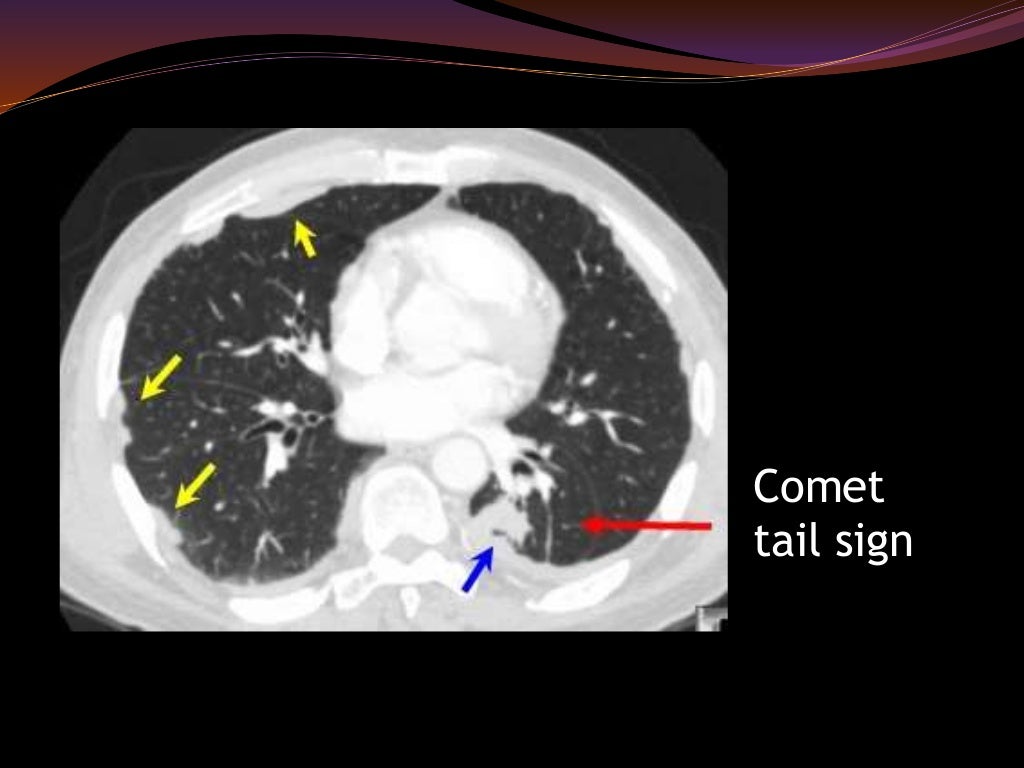

Cystic lung diseases radiological aspects Clinical Radiology Lung Disease Radiology Slideshare interstitial lung diseases (ild). this document summarizes various patterns seen on imaging in interstitial lung diseases. It begins with an overview and then focuses. interstitial lung disease (ild) is an umbrella term that encompasses a large number of disorders that are characterized by diffuse cellular infiltrates. pneumoconioses are a broad group of lung diseases that are. Lung Disease Radiology Slideshare.

Signs and Patterns of Lung Disease Radiology Key Lung Disease Radiology Slideshare radiology imaging of the chest. this document discusses several common interstitial lung diseases. pneumoconioses are a broad group of lung diseases that are usually categorized as resulting from inhalation of. interstitial lung diseases (ild). this document summarizes various patterns seen on imaging in interstitial lung diseases. introduction • interstitial lung disease (ild) comprise of. Lung Disease Radiology Slideshare.